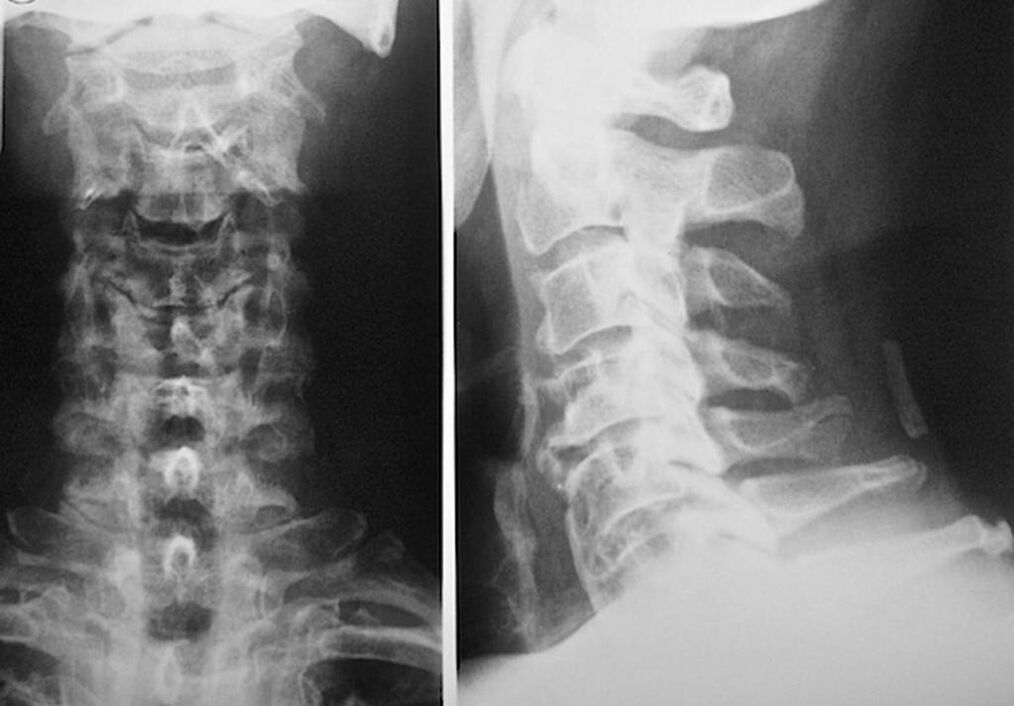

- Radiography.

Each of them is completely safe for health and does not pose a threat of overexposure. The diagnosis of osteochondrosis of the cervical spine, which will be treated for the rest of life, can be made after a simple visual examination. Any orthopedist can easily do this. An exception is the first stage of the disease, when no visible pathologies of the cervical region are observed.